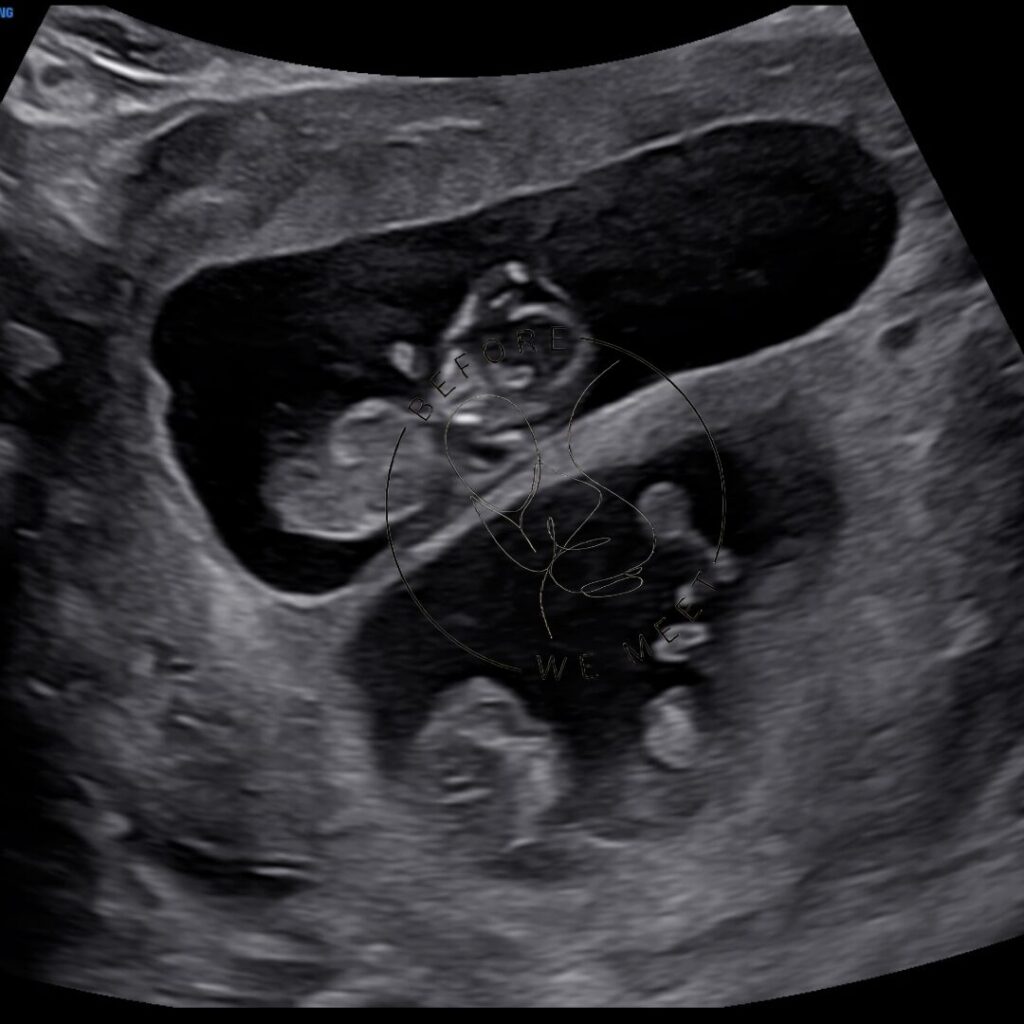

Veel ouders kiezen voor een pretecho als herinnering aan de zwangerschap of om samen met familie of vrienden extra naar de baby te kijken. Bij een 3D- of 4D-echo zien we duidelijk het gezichtje in kleur en zien we soms een lachje of een gaapje!

Een 3D/4D echo is éxtra bijzonder doordat we de baby met al zijn of haar details kunnen zien in stilstaande en bewegende beelden. Op wie lijkt zijn/haar neusje? Heeft hij/zij al bolle wangetjes? Of misschien zien we de baby zelfs wel drinken of lachen? Het laat jou (en ons!) verwonderen hoe magisch het nieuwe leven dat in je buik groeit is!

2D pretecho